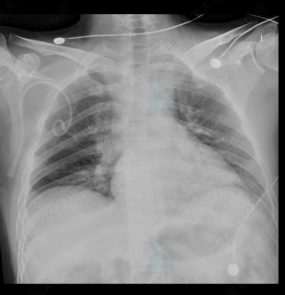

放置闭式引流后胸片提示气胸消失、肺复张良好

前日胸外科收治了一位36岁青年男性和一位55岁中年女性。两位患者均为新冠阳性患者,在居家过程中咳嗽及体位改变后出现胸痛、气短症状前来就诊。经由急诊科分诊,根据典型症状、查体结合胸部CT诊断为气胸,诊断后行闭式引流术,治疗后胸闷气短症状明显缓解,呼吸轻快有力,预后良好。